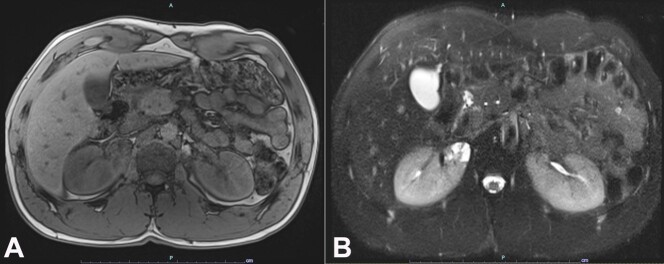

局部囊性肾病(LCKD)是一种独特的肾脏疾病,其特点是在肾脏的特定区域出现囊肿。我们介绍了一例罕见病例,患者是一名 41 岁的非裔美国男子,因出现下尿路症状和毛细血尿而到我们的医疗中心就诊。经过初步评估,最终确诊为无并发症的尿路感染,并给予适当的口服抗生素治疗。5 个月后的随访中,患者又出现了毛细血尿。影像学检查发现,右肾极间区有一个 2.6 厘米的混合密度囊性病变。该囊性病变在肾脏上端有复杂的间隔。患者在机器人辅助下进行了右肾部分切除术,病理检查确诊为 LCKD。本报告不仅强调了 LCKD 的独特性,还全面回顾了与此病相关的现有文献。报告特别强调了LCKD固有的良性特征,以及它与其他肾脏疾病常见的进行性发展轨迹的明显不同。我们还探讨了该病的偶然发现、其不同的临床症状、可想象的病因基础以及所使用的一系列诊断方法。最后,我们讨论了组织病理学发现与多囊肾和其他疾病的相似之处,强调了准确诊断和管理的重要性。

Localized cystic kidney disease (LCKD) is a distinct renal disorder characterized by the presence of cysts within specific regions of the kidneys. We present a rare case of a 41-year-old African American man, who presented to our medical center with lower urinary tract symptoms and gross hematuria. The initial assessment culminated in the identification of an uncomplicated urinary tract infection, prompting the prescription of appropriate oral antibiotic therapy. On follow-up after 5 months, the patient presented with gross hematuria. Imaging studies revealed a mixed-density cystic lesion of 2.6 cm situated within the interpolar region of the right kidney. This cystic lesion exhibited intricate septations at the superior pole of the kidney. Robotic-assisted right partial nephrectomy was performed, and pathologic examination was diagnostic for LCKD. This report not only underscores the uniqueness of LCKD but also presents a comprehensive review of the existing literature that pertains to this condition. Particular emphasis is placed upon its inherent benign behavior and its marked divergence from the progressive trajectory commonly associated with other renal diseases. We also explored the incidental findings of the disease, its diverse clinical symptomatology, conceivable etiological underpinnings, and the array of diagnostic modalities used. Finally, similarities in histopathologic findings with polycystic kidney disease and other entities are discussed, underscoring the importance of accurate diagnosis and management.